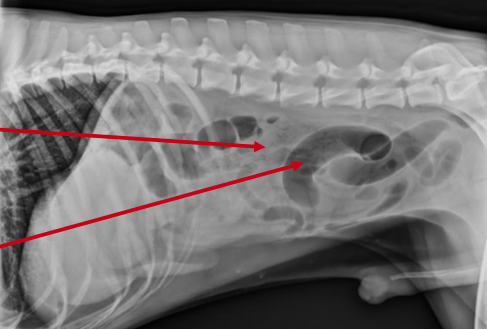

Radiology Result: Radiographs (X- rays) are electromagnetic waves that pass through patients to form an im- age of the internal structures.

- Intraluminal textile material in the small intestine: The alternating white and grey stripes in the small intestine are a pattern that fabric materials commonly form. (top arrow)

- Small intestine gas-filled and dilated: The dark tubular structures in Ca- nelo’s abdomen are dilated intes- tines. Dilated intestines can be evi- dence of an intestinal obstruction caused by a foreign body. (lower arrow)